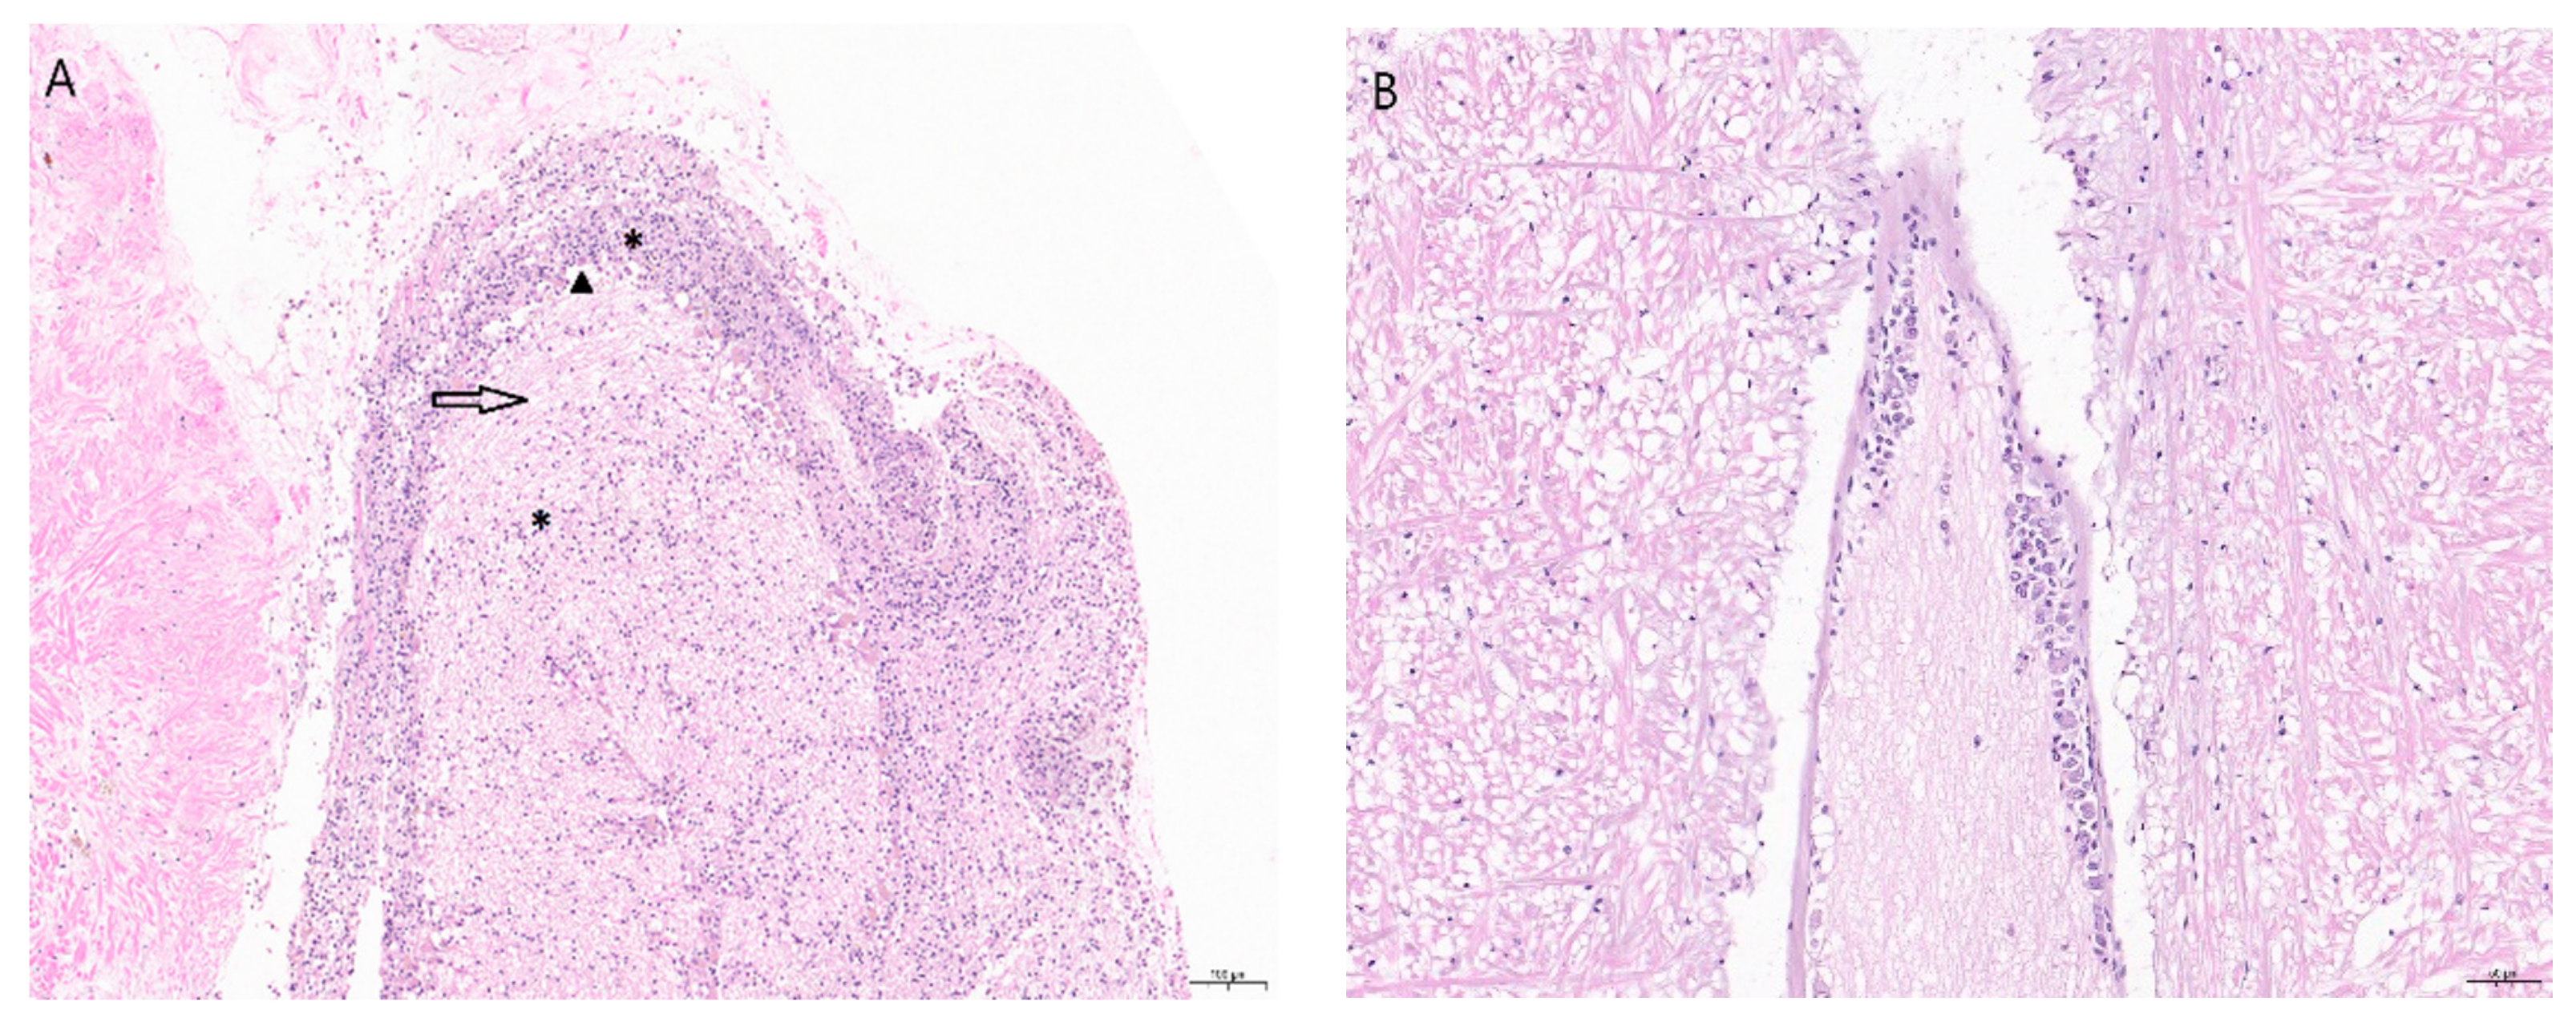

2. Clinical Signs and Pathology